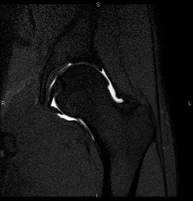

Exploració ideal per estudiar les lesions en músculs isquiotibials i quàdriceps, sovint lesionats en esportistes. També permet una bona valoració de tendons i de nervis perifèrics. La durada aproximada és de 20 minuts. No utilitza radiació ionitzan. - RM de Genoll

Exploració per estudiar lesions a l'articulació, com trencaments dels meniscals i dels lligaments creuats (únicament es poden detectar amb aquesta prova), condropatia o desgast del cartílag i moltes altres alteracions derivades de l'activitat esportiva i dels canvis degeneratius (osteoartrosi). La durada aproximada és de 18 minuts. No utilitza radiació ionitzant. - RM de Cama